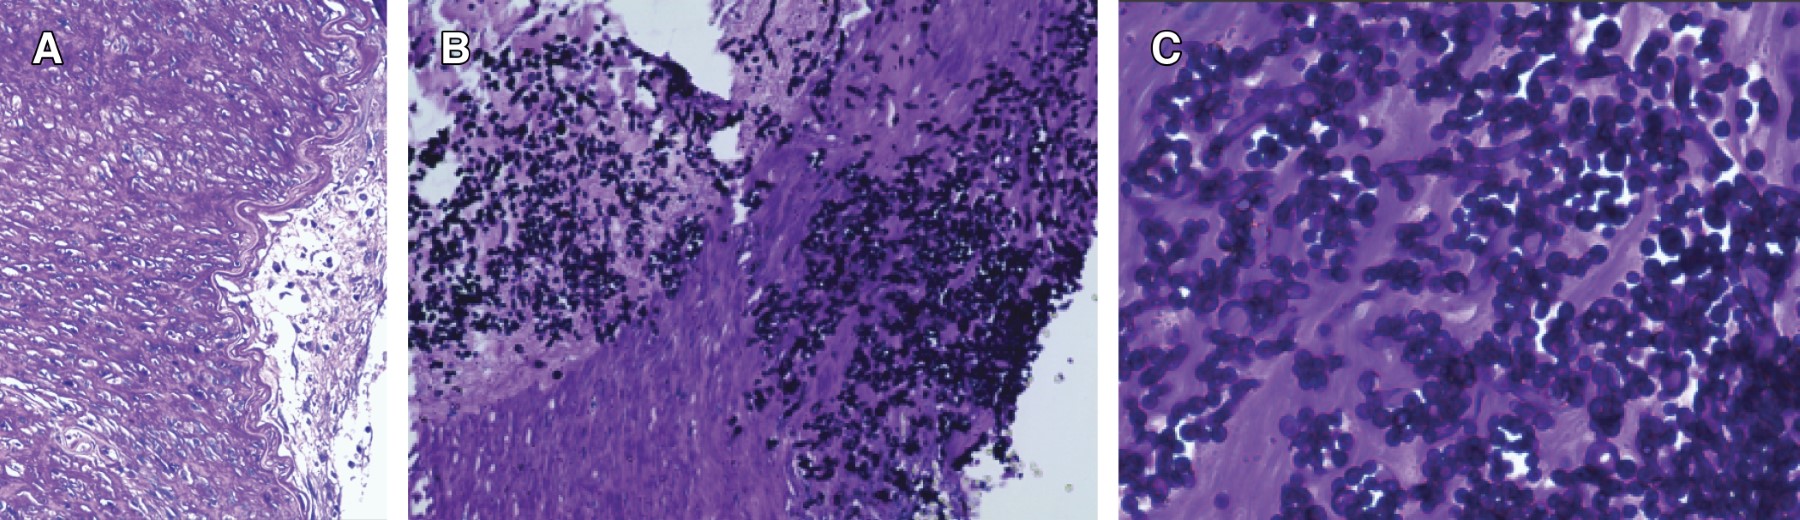

Introduction: graft function and survival in postransplant recipients are compromised in cases of invasive Candida sp. infection due to abrupt presentation and nonspecific symptoms. Approximately 1.3% of recipients will develop invasive fungal infection, 49% secondary to Candida albicans, followed by C. glabrata and parapsilosis. It is transmitted from donor to recipient in 0.001% of cases, only 65.4% receive antifungal treatment in the presence of positive perfusion fluid cultures. The incidence of invasive candidiasis is 0.001%, independent risk factors for C. albicans infection have not yet been identified. There are few reported cases of persistent infection and failure of vascular reconstruction after graft nephrectomy. Case report: 24-year-old female patient, diagnosed with lupus nephropathy, received a cadaveric donor kidney transplant without complications. Pre-transplant urine culture was positive for C. albicans, interpreted as contamination. The donor (21 years old, KDRI 0.66/KDPI 13%) presented pyelocaliceal dilatation due to probable ureteral stenosis, repaired during bank surgery. At 14 days he suddenly presented hypovolemic shock, the surgical exploration reported complete dehiscence of the arterial anastomosis with extension to the renal hilum. Graft nephrectomy and vascular reconstruction of the external iliac artery with PTFE patch was performed. The pathology of the graft reported hydronephrosis and acute/chronic granulomatous pyelonephritis associated with filamentous fungus, suggestive of Candida sp. Nine days later she presented sudden hypovolemic shock and cardio-respiratory arrest, open vascular exploration was performed, reporting PTFE patch dehiscence, external iliac artery resection was performed and distal vascular reconstruction with PTFE femoro-femoral bridge (banded, 10 mm), confirming Candida albicans invasion by histopathology and cultures. He started anidulafungin, was adjusted to Fluconazole, completing six weeks of treatment. Two months of follow-up without recurrence. Discussion: invasive infection by Candida sp. frequently presents unfavorable outcomes with any type of treatment in terms of graft and patient survival. Few cases require additional interventions due to persistence of the infection. Trans-surgical macroscopic assessment does not correlate with the degree of infection, so it is difficult to determine the extent of resection. Even with the risk of contamination of the synthetic vascular material, adequate short-term success rates have been reported. Conclusion: aggressive surgical treatment could improve patient survival outcomes. Performing native vessel resection and distal revascularization initially could be a valid option in selected cases. We should not underestimate the impact of positive pretransplant cultures, even in the absence of symptoms. It is recommended to send native tissue samples to rule out residual candidiasis. Close follow-up is required when using synthetic materials for vascular reconstruction. A consensus has yet to be reached to determine the best management for cases of invasive candidiasis and thus improve outcomes in terms of graft function, due to the high rate of nephrectomies performed.

Figure 1

Figure 2

Figure 3